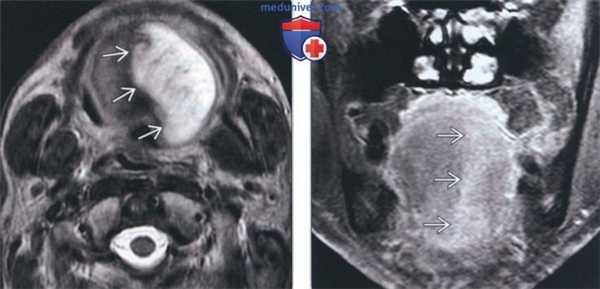

По данным МРТ головного мозга с усилением сигнала парамагнетиком выявлена опухоль парастволовой локализации справа, компримирующая продолговатый мозг и исходящая из расширенного канала подъязычного нерва. Меньший по размерам компонент опухоли располагался в полости канала и распространялся экстракраниально (рис. 1). Рис. 1. МРТ головного мозга пациентки В. до операции. При усилении сигнала выявляется опухоль справа, соответствующая невриноме, в форме «гантели», располагающаяся одной частью на уровне краниовертебрального перехода и вызывающая компрессию ствола мозга, а другой — частью в костных структурах.

При СКТ головного мозга в костном режиме выявлен расширенный канал подъязычного нерва с деструкцией его стенок. Заднелатеральная стенка практически отсутствовала, вследствие чего полость канала сообщалась с просветом яремного отверстия (рис. 2). Рис. 2. СКТ головного мозга пациентки В. в костном режиме до операции. Определяется деструкция канала подъязычного нерва справа, канал отделен от полости яремного отверстия тонкой костной перегородкой (указано стрелкой).